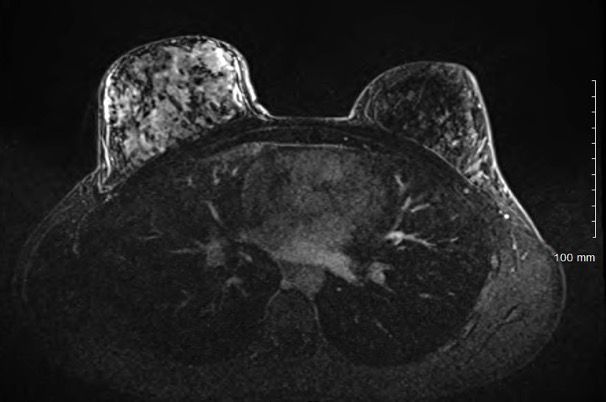

A 22-year-old Caucasian woman presented with a four month history of pain, tenderness and swelling in her right breast. Initial treatments with antibiotics and steroids were unhelpful. She had continued to have diffuse swelling and tenderness in her right breast and also noted bruising on the overlying skin. An ultrasound of the right breast showed a large, diffuse, irregular, echogenic lesion, suggesting inflammation or tumor. A mammogram confirmed diffuse mass-like density corresponding to the echogenic mass seen on the ultrasound. A bilateral breast magnetic resonance imaging (MRI) reported diffuse abnormal signal and enhancement throughout the entire right breast (Figure 1). A right breast needle biopsy was performed (Figure 2).

Based on the images shown, what is your diagnosis?